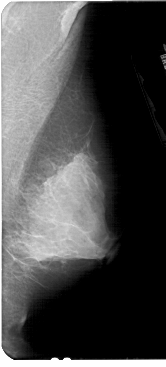

A_1927_1.LEFT_MLO

LEFT_MLO LINES 5326 PIXELS_PER_LINE 2386 BITS_PER_PIXEL 12 RESOLUTION 43.5 OVERLAY